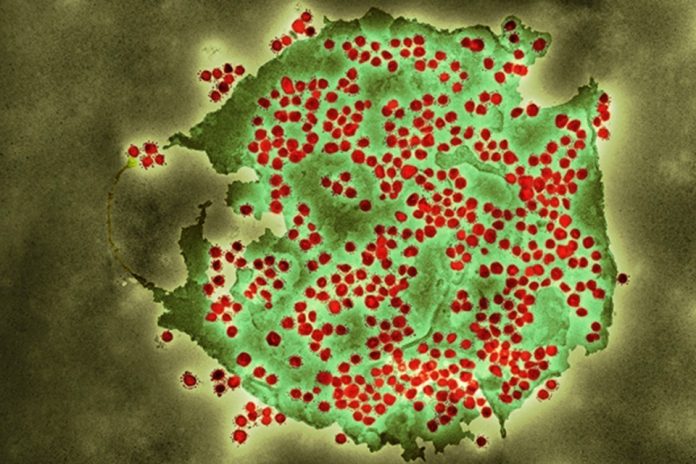

LONDON, England – The Omicron variant sub-lineage known as BA.2 has been designated a variant under investigation ( VUI-22JAN-01) by the UK Health Security Agency (UKHSA).

“Overall, the original Omicron lineage, BA.1, is dominant in the UK and the proportion of BA.2 cases is currently low. The designation was made on the basis of increasing numbers of BA.2 sequences identified both domestically and internationally. There is still uncertainty around the significance of the changes to the viral genome, and further analyses will now be undertaken,” explained, “To date, there have been 426 cases of Omicron BA.2 confirmed by Whole Genome Sequencing (WGS), with the earliest dated December 6, 2021.”

“It is the nature of viruses to evolve and mutate, so it’s to be expected that we will continue to see new variants emerge as the pandemic goes on. Our continued genomic surveillance allows us to detect them and assess whether they are significant. So far, there is insufficient evidence to determine whether BA.2 causes more severe illness than Omicron BA.1, but data is limited and UKHSA continues to investigate. Case rates remain high throughout the UK and we must remain vigilant and take up vaccinations. We should all continue to test regularly with LFDs and take a PCR test if symptoms develop.”

UKHSA noted that the areas with the largest number of confirmed cases are London (146) and the South East (97). Data for the devolved administrations will follow in due course. Early analyses suggest an increased growth rate compared to BA.1, however, growth rates have a low level of certainty early in the emergence of a variant and further analysis is needed.

“In total, 40 countries have uploaded 8,040 BA.2 sequences to GISAID since 17 November 2021. At this point it is not possible to determine where the sublineage may have originated. The first sequences were submitted from the Philippines, and most samples have been uploaded from Denmark (6,411). Other countries that have uploaded more than 100 samples are India (530), Sweden (181), and Singapore (127). Omicron BA.2 lacks the genetic deletion on the spike protein which produces S-gene target failure (SGTF) in some polymerase chain reaction (PCR) tests, which has been used as a proxy for Omicron cases previously,” reads UKHSA statement.